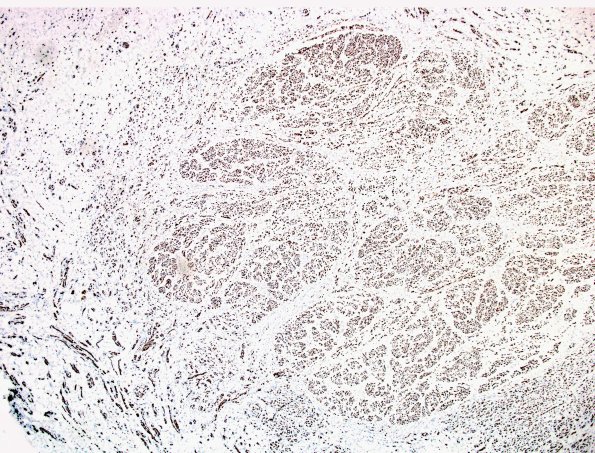

4B1-3 A neuroma is rich in axons since they result in its formation and are dispersed with the mini-fascicles. (NF IHC)